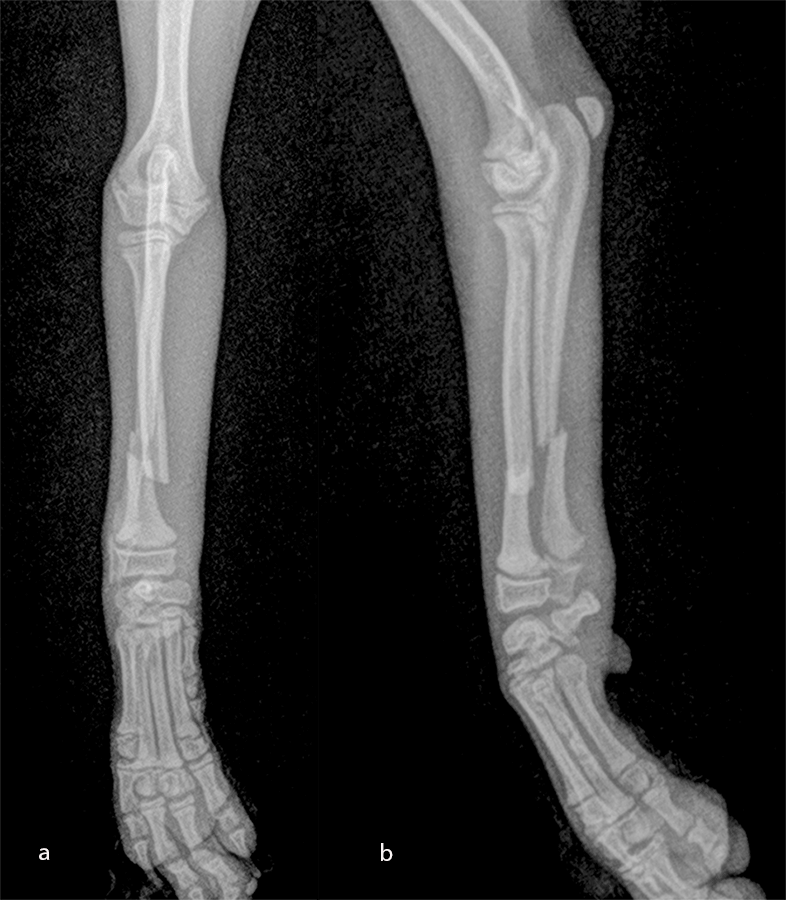

The patient was a 6-month-old, 1 kg (exactly 0.950 kg) Pomeranian dog presenting with a radial fracture of the left thoracic limb after a jump from ≈ 50 cm. The 1.5 mm System was too large for the width of the radius (2.2 mm) and the width of the radial medullary canal (0.5 mm) (Fig 7). The 1.3 mm adaptation plate was a perfect plate for this fracture. This plate option permitted the use of cortex and locking screws.